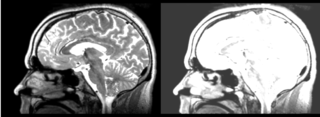

Original file(1,162 × 426 pixels, file size: 306 KB, MIME type: image/png)

Registration of a t2w image to arbitrary t1 and back via the BSpline selection in the Register Images module.